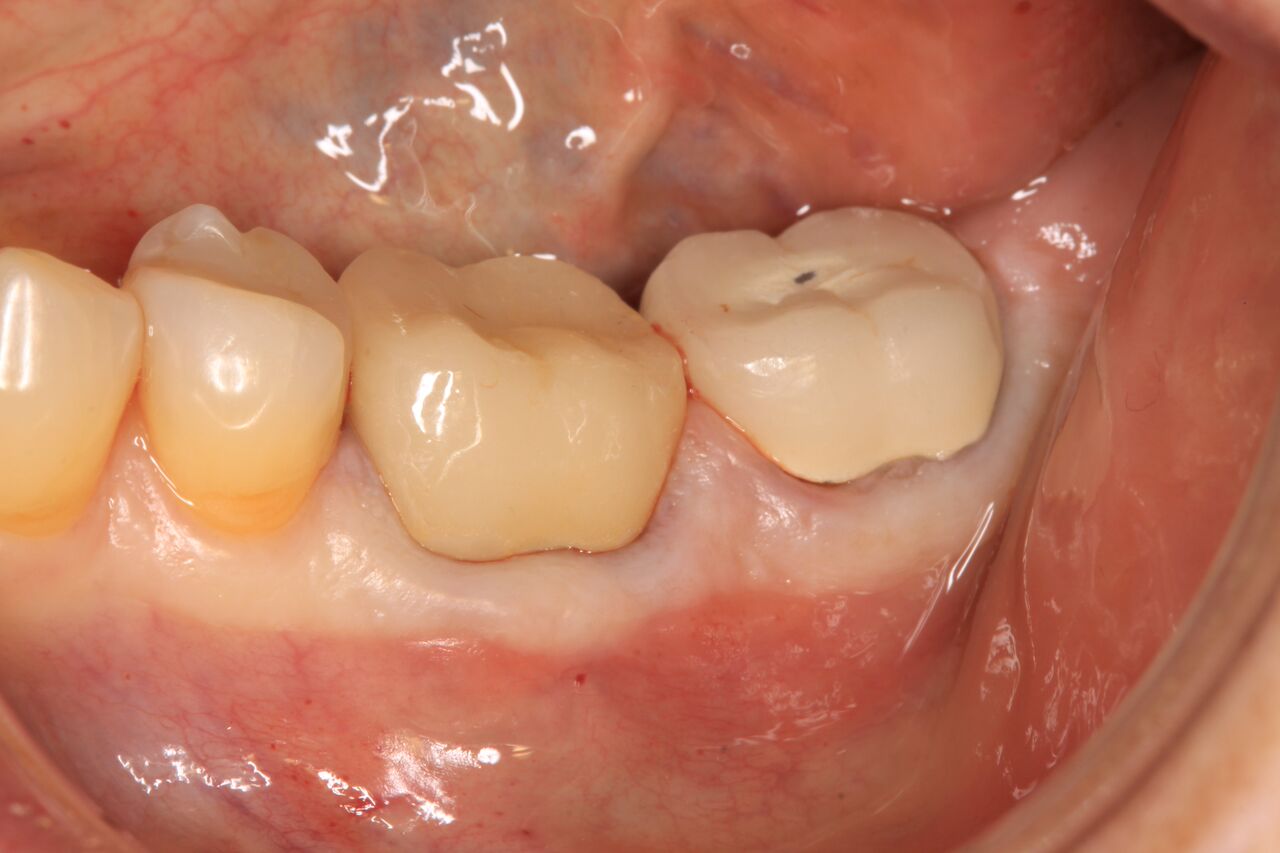

(5.) Immediate restoration of No. 19 day of surgery in infraocclusion.

Figure 5

(7.) 1-year clinical postoperative of No. 19 restoration.

Figure 7

A 63-year-old woman presented with severe pain on biting of tooth No. 19 (Figure 1). Clinically there was pain on percussion and significant periodontal probing along the mesial root. The patient was anesthetized with infiltration anesthesia and the crown was horizontally sectioned from the lingual of the tooth. The remaining tooth was sectioned so the roots could be extracted individually. The socket was fully debrided and an implant was placed (Figure 2), which was prosthetically correct and stabilized in excess of 45 Ncm. The bone was milled to allow for unimpeded placement of a temporization abutment. The initial crown was revised to be the temporary crown in infraocclusion. Cement was extruded extraorally (Figure 3) prior to seating of the temporary restoration. The socket was sealed with the temporary crown and there were no sutures or bone graft (Figure 4 and Figure 5).

The patient was instructed in postoperative care specific to an immediately provisionally restored implant and an antibiotic and analgesic was prescribed. At 4 months, integration was confirmed. The patient was impressed for a final restoration that was cemented within 2 weeks. The final radiograph (Figure 6) and clinical photo (Figure 7) presents a 1-year postoperative demonstrating good esthetics, full bone regeneration, and a steady state of bone to the implant under loading.